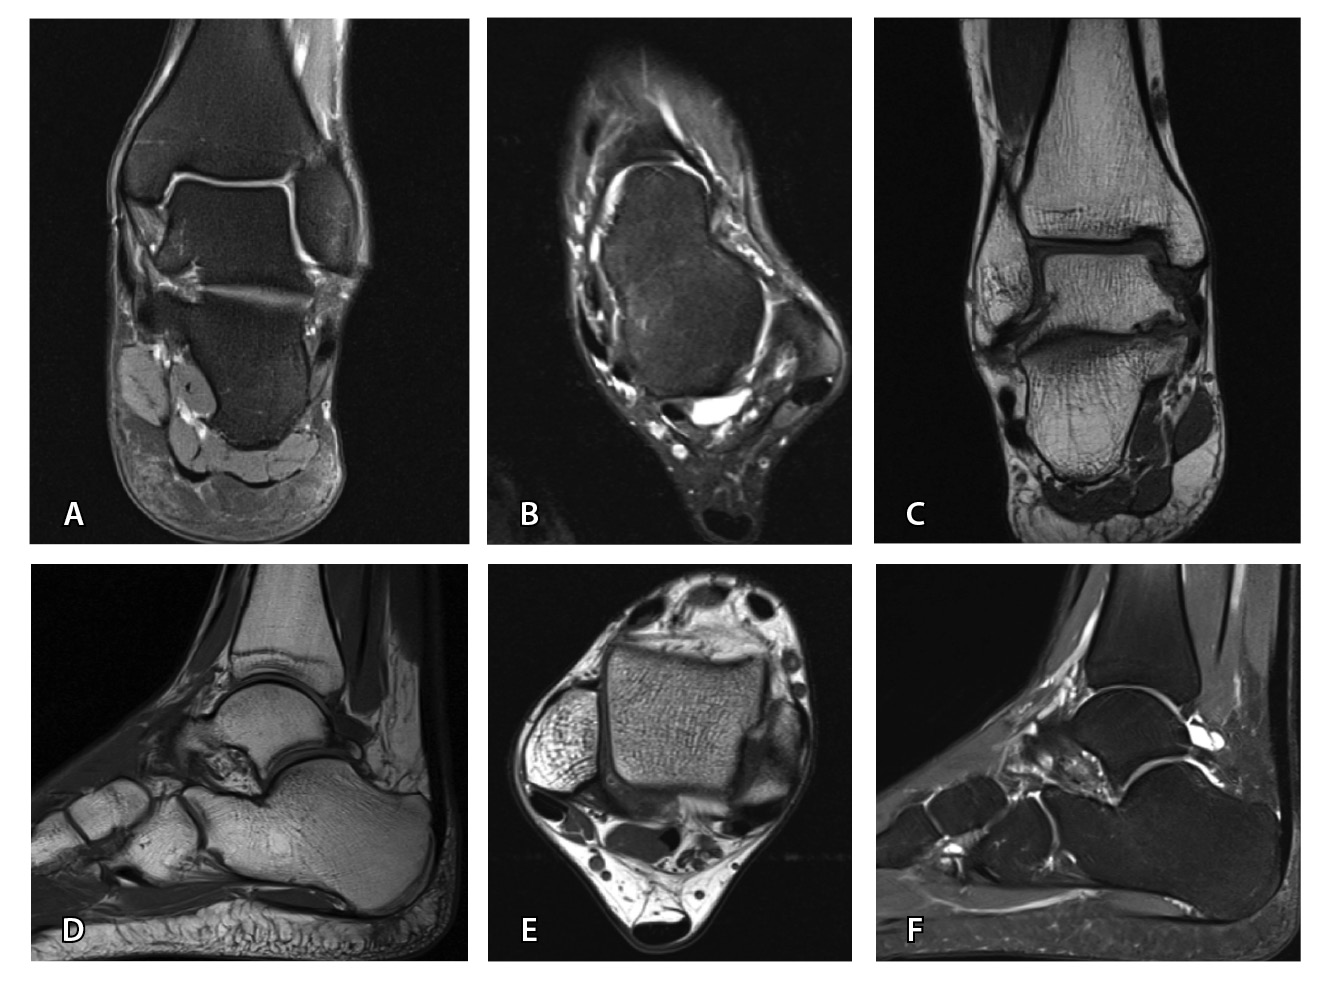

Важным условием для получения информативных МРТ-изображений является правильная укладка пациента и соблюдение стандарта сканирования: различия в натяжении или слабости связок при подошвенном или тыльном сгибании могут влиять на интерпретацию и приводить к ложноположительным или ложноотрицательным результатам [39, 52]. Магнитно-резонансное исследование выполняется лежа на спине с нейтральным положением голеностопного сустава и стопы. Рекомендации Европейского сообщества мышечно-скелетных рентгенологов 2016 г. (англ. European Society of Musculoskeletal Radiology, ESSR, 2016) по стандартному протоколу сканирования голеностопного сустава и костей предплюсны приведены в табл. 3 и на рис. 5 [56].

Рис. 5. Стандартный протокол магнитно-резонансной томографии голеностопного сустава согласно рекомендациям ESSR (2016): А – COR FS, Б – AX FS, В – COR T1, Г – SAG T1, Д – AX PD, Е – SAG STIR; AX – аксиальная, COR – корональная, FS – жироподавление, PD – протонная плотность, SAG – сагиттальная, STIR – инверсия-восстановление спинового эха